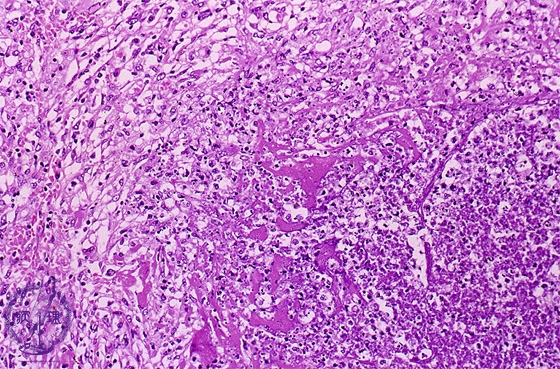

- ★(7)Bacterial pneumonia (lung abscess)

Microscopic view (HE stain, high power view): On the right, there is abscess composed of inflamed necrotic debris (dotted line) surrounded by granulation tissue (left). Granulation tissue consists of fibroblasts, inflammatory cells and capillaries.